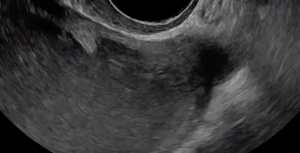

Although not clearly depicted in this clip, deep endometriosis likely is present posterior to the uterus at the level of the internal cervical os, as demonstrated by the irregular, hypoechoic area.

In this case, there is a fixed ovary posteriorly and subtle hypoechoic nodule posterior to the uterus at the level of the internal cervical os, suggesting of deep endometriosis of the torus uterinus.